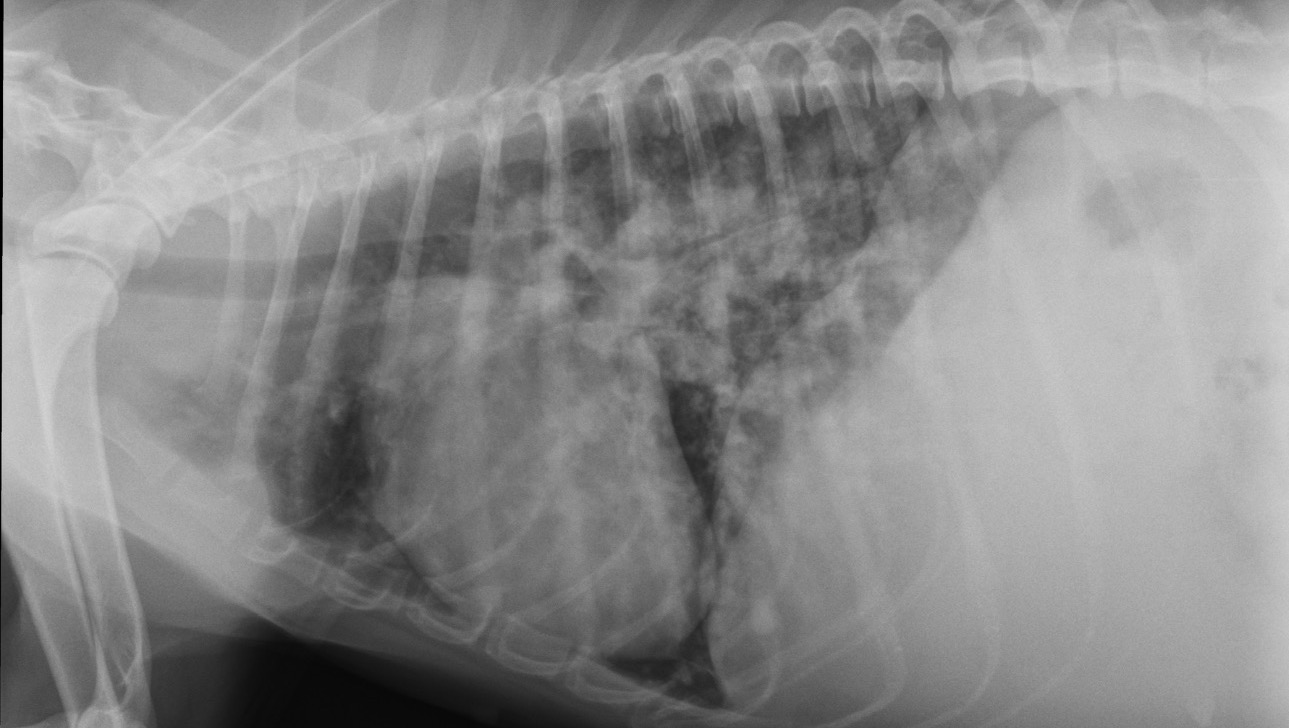

Hola, me llamo Rocío y hace unos meses rescaté a esta preciosa peludita. Había sido abandonada en el campo en muy malas condiciones. Desnutrida, con calvas en el pelaje y prácticamente ciega. Dio positivo en leishmaniosis. Ahora ha dado positivo en filaria en estado muy avanzado, la enfermedad no dio la cara antes. Está ingresada porque tiene muchos gusanos comprometiendo la vena cava, lo que le ha provocado una ascitis por insuficiencia cardiaca. Necesita cirugía de urgencia pero el costo de la operación es elevado. La operación es en Portugal y tiene un costo de 4.000€ más desplazamiento y hospitalización. Estoy a la espera de recibir el presupuesto final.